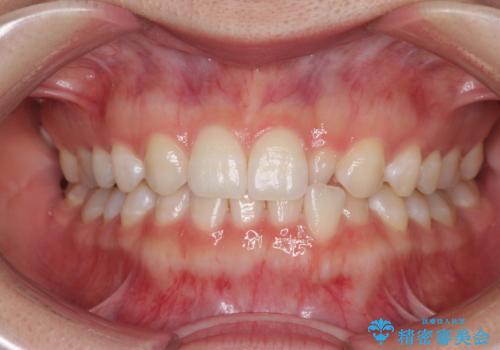

前歯の反対咬合 非抜歯のワイヤー矯正

海外転居前に気になる前歯を整えたい 上下前歯の部分矯正